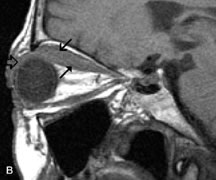

Tl relaxation time is the time required for the energized nuclei to give up the excess energy that was acquired from the RF pulse (high-energy state) and re-establish equilibrium (low-energy state) with the main magnetic field. The excess energy is released by these excited nuclei to the surrounding molecular environment, or lattice, and results in T1 relaxation, also called spin-lattice relaxation time. In different biologic tissues, hydrogen has a Tl ranging from a few hundred milliseconds to a couple of seconds. This range exists because local tissue factors affect the ability of specific protons to give up energy to the surrounding tissues. For example, hydrogen atoms attached to the carbon atoms of fat molecules relax much more rapidly than those attached to the oxygen atoms of water molecules. Viscosity, concentration, temperature, and molecular environment of the hydrogen atoms in the tissues also affect the T1 relaxation time. On a T1-weighted orbital image, fat, which has a very short T1 relaxation time, yields a high-intensity signal; the rectus muscles, which have an intermediate T1, yield an intermediate-intensity signal; and the vitreous, which has a long T1, yields a low-intensity signal (Fig. 8).5,8,16